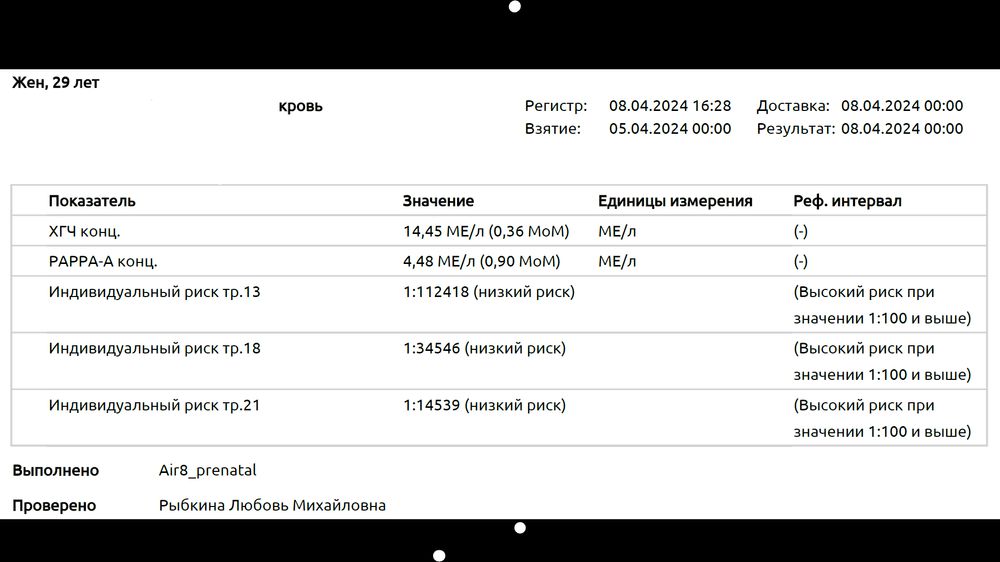

Моя криветка дрегался и поворачиваться не хотел нормально) Смогла поймать только в такой смешной позе)) По УЗИ все отлично, ПДР поставили на 2 дня раньше)) Ждём результатов крови))